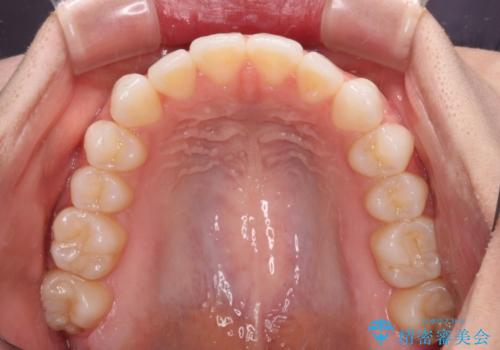

上下前歯が接触しない オープンバイトをインビザラインで改善

- 前歯の上下スペースによる食べにくさを気にして来院された患者様です。

インビザラインにより上下の前歯の隙間を閉じていくこととしました。

上下の奥歯を圧下させるようにすることで、前歯を接触させるように計画しました。

上下の隙間に舌が入り込むことがオープンバイトの原因であったため、舌の筋肉のトレーニングも並行して行い、後戻りの抑制を図りました。